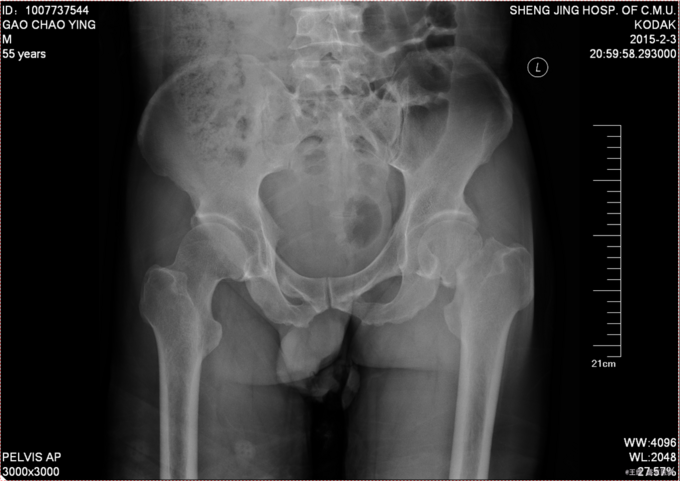

患者自述于2015-12-3日15时在工厂干活时不慎由梯子上摔落(高约3米),致左髋部疼痛、活动受限,不能站立行走,急送至当地医院行骨盆DR示:左股骨颈骨折。现患者为求进一步诊治来我院,急诊以“左股骨颈骨折”为诊断收入我科。患者自受伤以来一般状态可,无发热,无头晕、呕吐,无胸闷、心悸呼吸困难,无腹痛、腹泻,饮食可,睡眠可,二便正常。

专科查体:患者平车入病房,左小腿胫骨牵引中,右下肢外展、外旋约45度,患肢缩短约1cm 右髋部疼痛,压痛(+),右下肢感觉未见异常,活动可,双侧足背动脉搏动可触及。